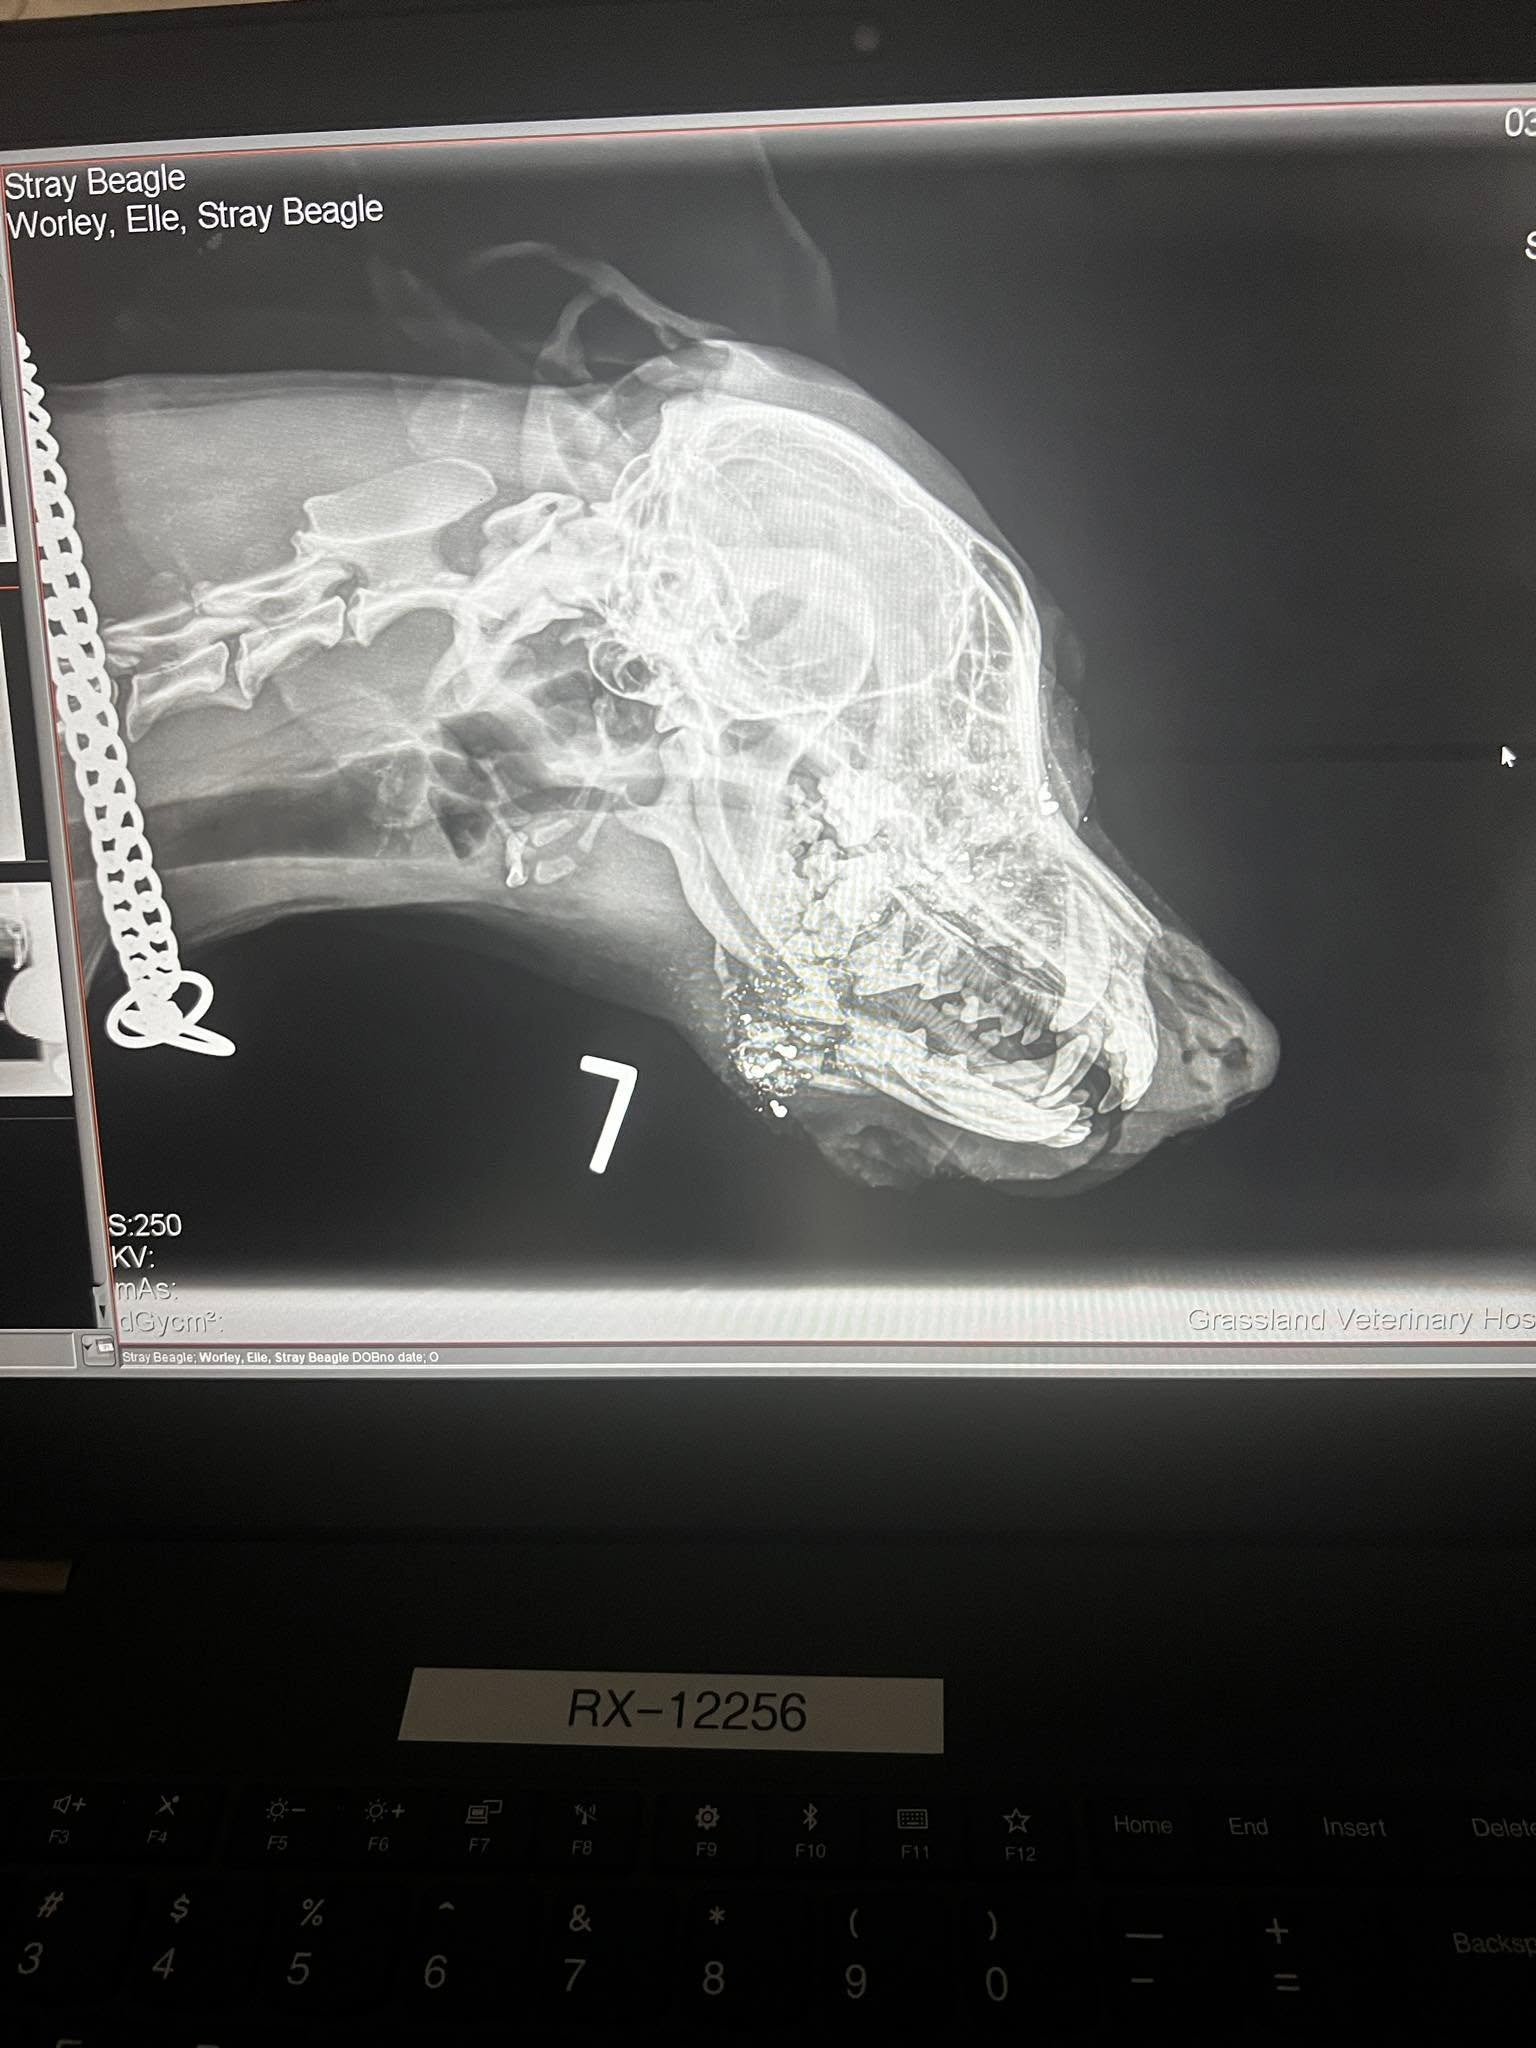

A trip to the veterinarian in Broken Bow a short time later revealed that Juni had been shot in the head and that the right side of her jaw was shattered.

After a referral to a dental and oral surgeon in Omaha and a drive that began at 2:30 AM the next morning, what Juni had experienced became clearer: two shots with a .22 caliber bullet had missed her brain and eye by just centimeters.

Under anesthesia, more extensive x-rays were completed and Juni’s jaw was cleaned out but a reconstruction couldn’t be done that day. The little dog needed time to heal.

“Because of the gunshot wound, the teeth lost blood flow. So we don’t know if we’ll have to extract the teeth, again a wait-and-see scenario. There was also some fragmentation that was in her nasal cavity that the vet said worst case scenario could cause chronic infections but obviously we hope that that’s not the case,” Worley explained.